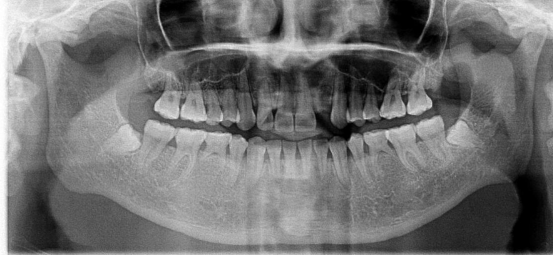

全景片:

顧名思義(yi) ,就是可以看到的全口牙齒情況的片子,不僅(jin) 可以看到牙齒,還能看到牙齦下的牙根情況,以及牙槽骨情況,對於(yu) 全口牙齒的健康情況了如指掌。使用比較廣泛,通常用於(yu) 查看智齒/多生牙(拔牙)、牙齦萎縮和牙槽骨吸收(牙周病治療)、正畸/種植牙等情況。